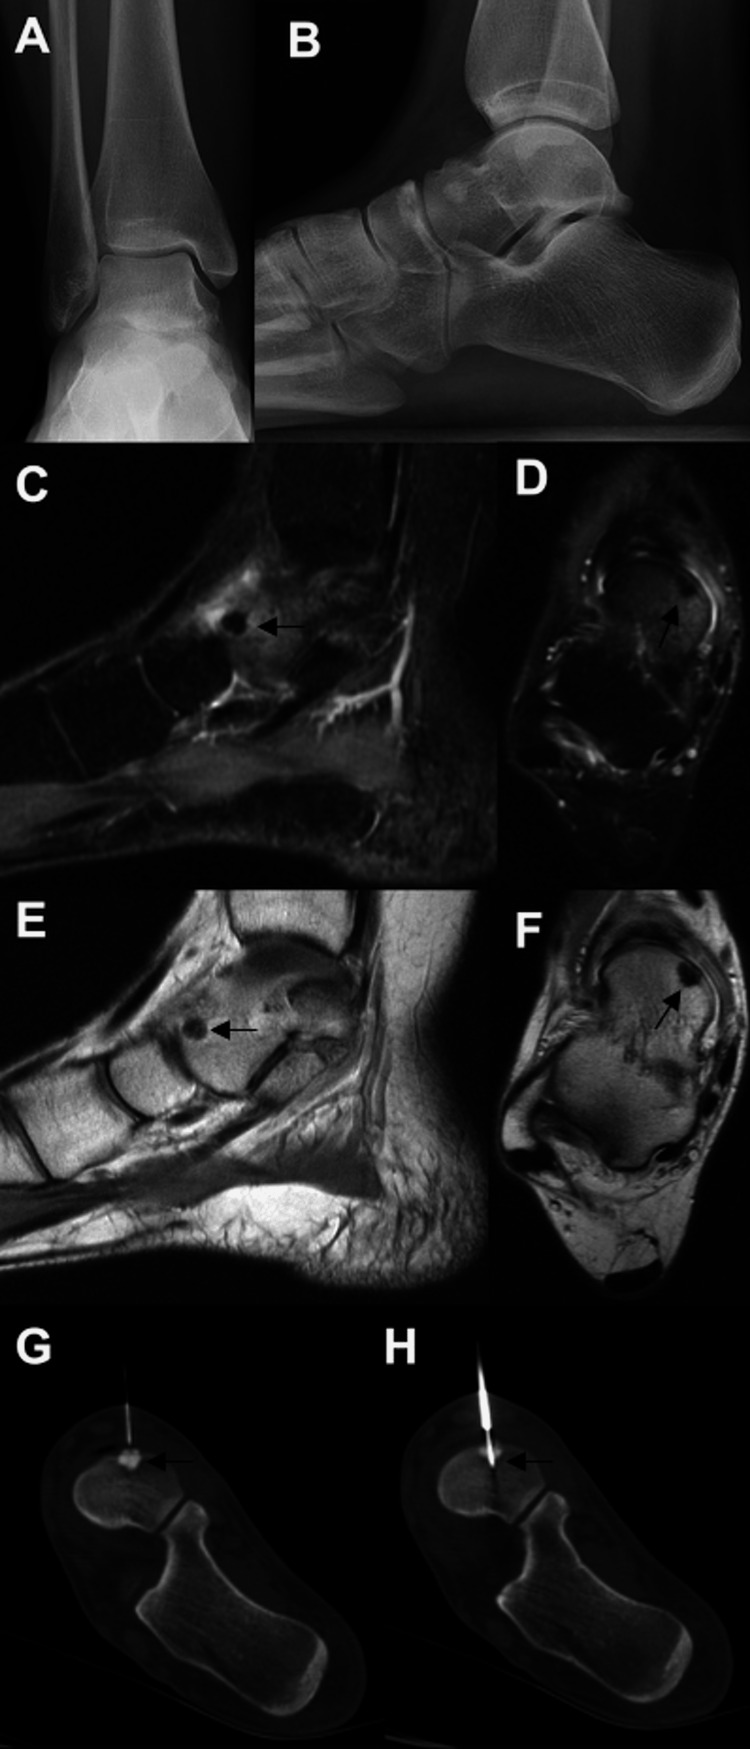

Figure 1. Images of the patient discussed in case one.

Initial weight-bearing AP (A) and lateral radiographs (B) were unremarkable. The osteoid osteoma lesion is better delineated on the MRI; sagittal inversion recovery (C), axial proton density (D), and sagittal proton density (E) images are shown. The lesion was also seen on the weight-bearing axial CT (F). Intra-procedure CT images demonstrate successful targeting of the lesion with RFA (G, H).

MRI: magnetic resonance imaging; CT: computed tomography; RFA: radio-frequency ablation